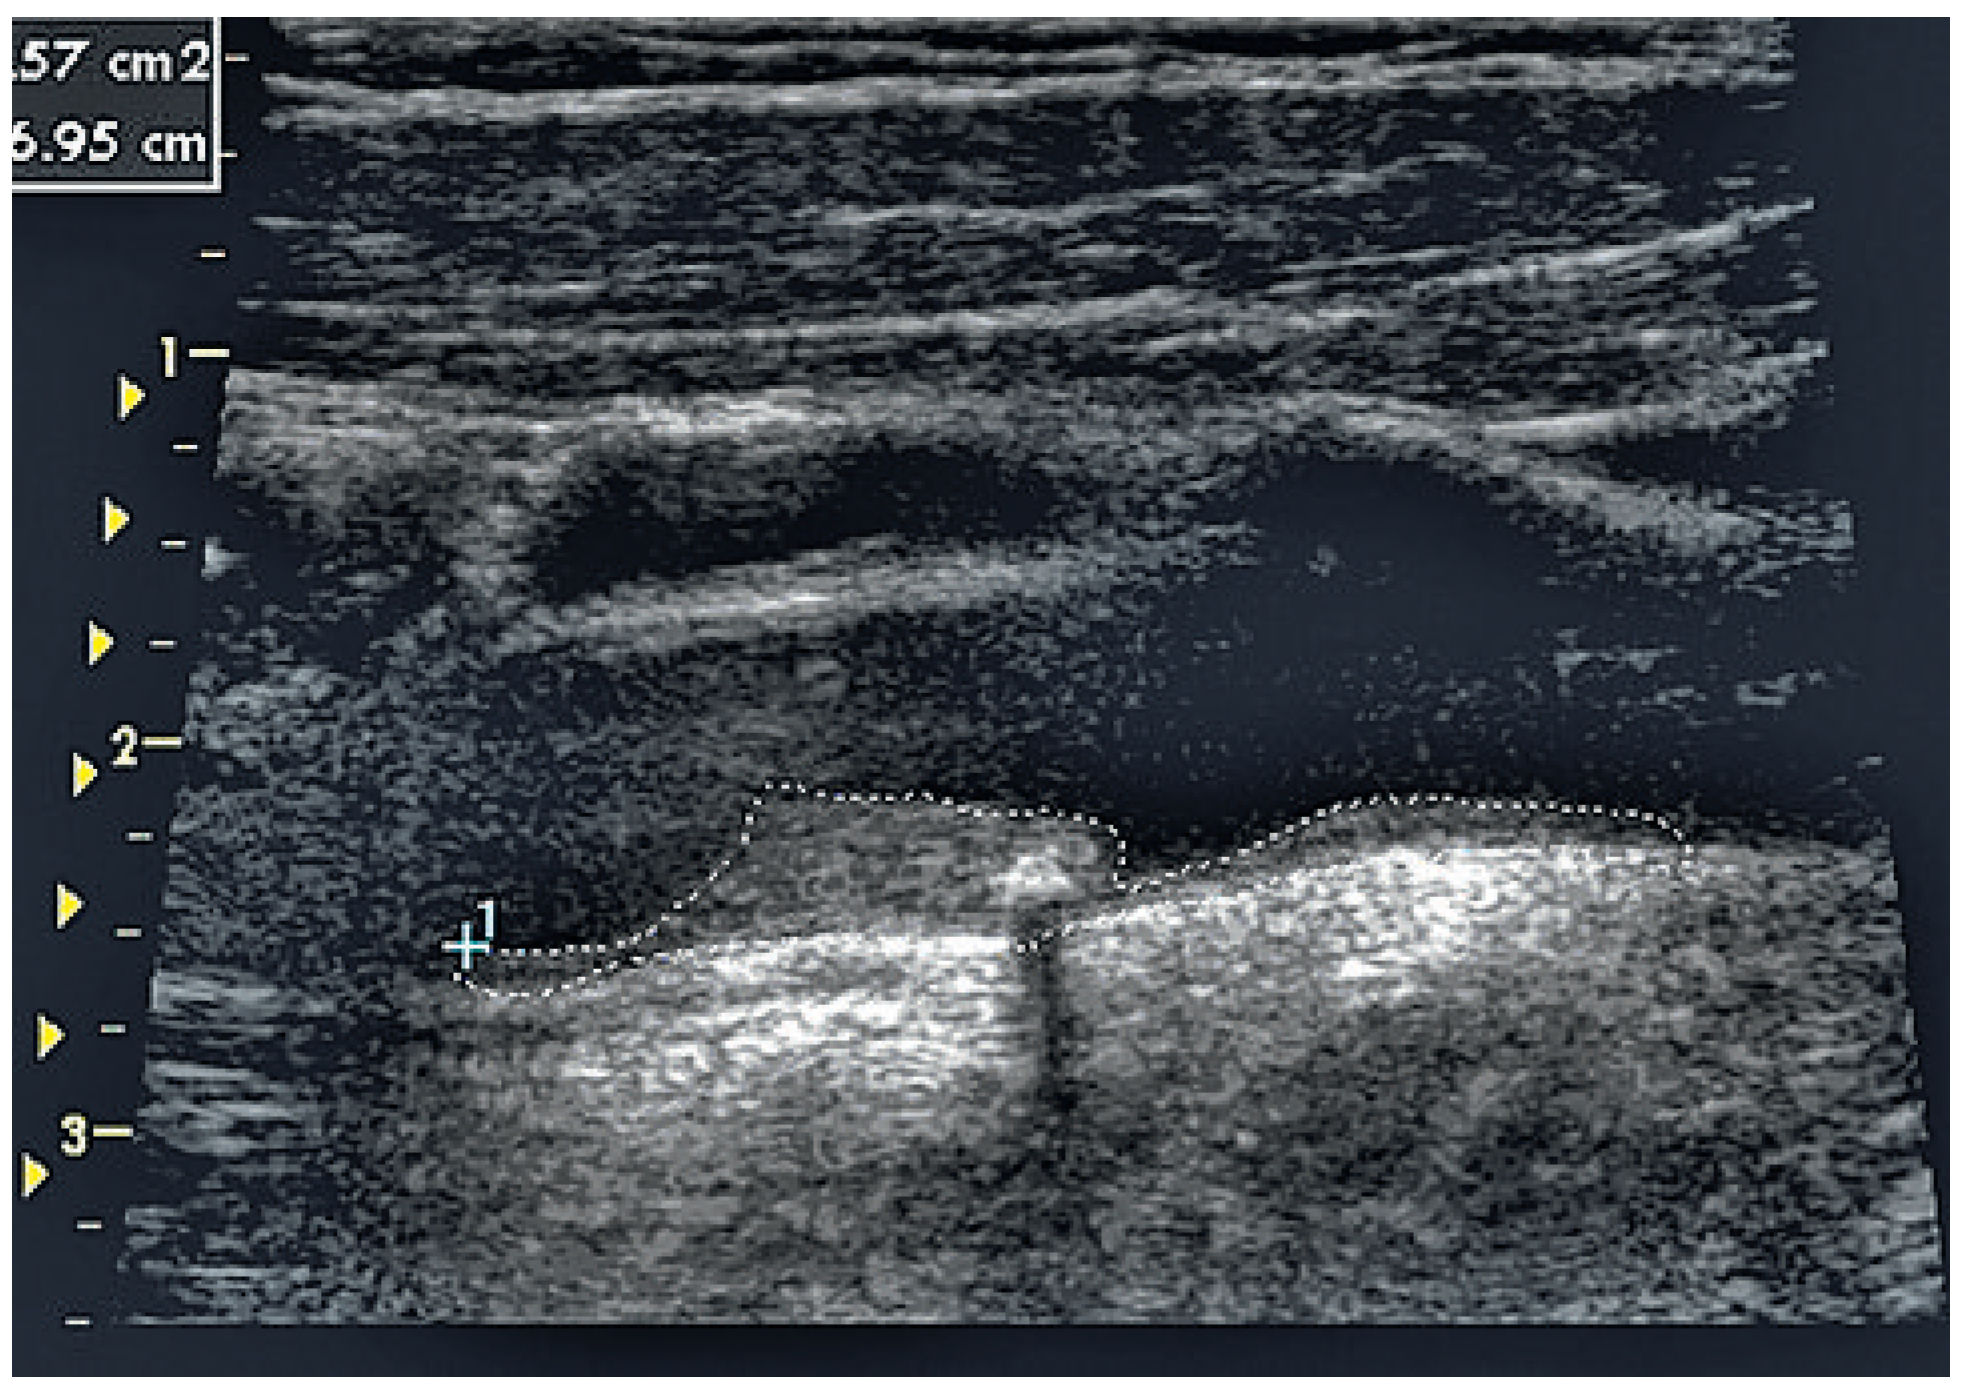

Imaging method and risk assessment using total plaque area of carotid arteries.